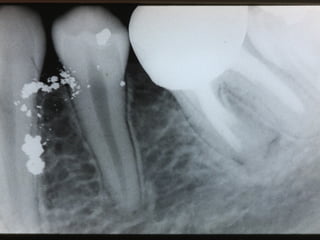

Tatuagem por Amalgama

• Retro-obturação Endodontica

• Aspectos Clínicos Radiográficos